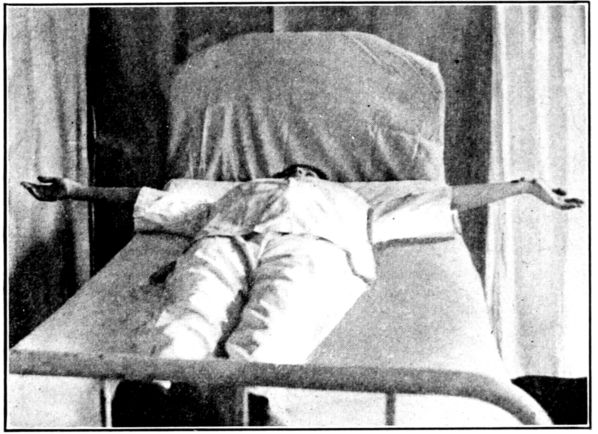

| 129, 130, 131, 132, 133, 134, 135. | Bed exercises taken during the puerperium | 350 to 353 |